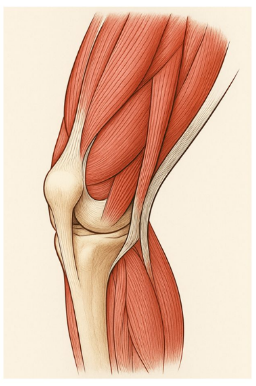

保存療法の中心となるのがリハビリテーションです。理学療法士の指導のもと、筋力強化や動作訓練を行います。硬くなった筋肉や腱を直接手でほぐすことで、症状の緩和も期待できます。多くの方が「太ももの筋トレが大事」と思われていますが、それ以前に膝関節の動きを改善することが重要です。

関節の動きが整うことで、過度な負担を減らすことができます。さらに、膝関節は股関節や足首、姿勢とも密接に関係しているため、膝だけでなく、身体全体を調整する視点も大切です。